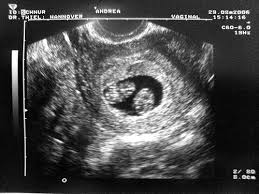

It might not come as a surprise that the presence of two babies exacerbates these symptoms. If you have tender painful and even slightly larger swollen breasts it can be a huge sign of twins. Symptoms of twin pregnancy at 5 weeks. Early signs of twins 5 weeks of pregnancy show that the size of a seed baby increases with intense development.

These early pregnancy signs hint you about your twins. There is no such progress in 5 weeks but the seed starts taking shape of a baby and embryos to have their own placenta and amniotic sac by the 5 weeks of pregnancy. Morning sickness food cravings fatigue frequent urination all are commonly experienced by pregnant women. 5 8 weeks pregnant with twins.

It can be difficult to establish a baseline for morning sickness as it can vary from person to person as well as from pregnancy to pregnancy. Higher hcg levels result in extreme morning sickn ess during the first two weeks of pregnancy. However you will show sooner than if you were carrying a singleton. Hearts start to beat.

Whether you are expecting one baby or twins the signs and symptoms of pregnancy will mostly be the same. And extreme nausea may set in even before missing periods. If you are pregnant with twins fatigue and exhaustion will be your constant companions.